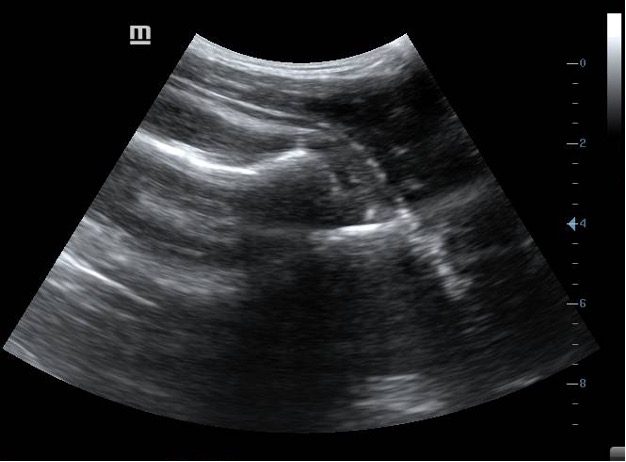

Figure 2. Position of probe across the posterior aspect of the shoulder joint